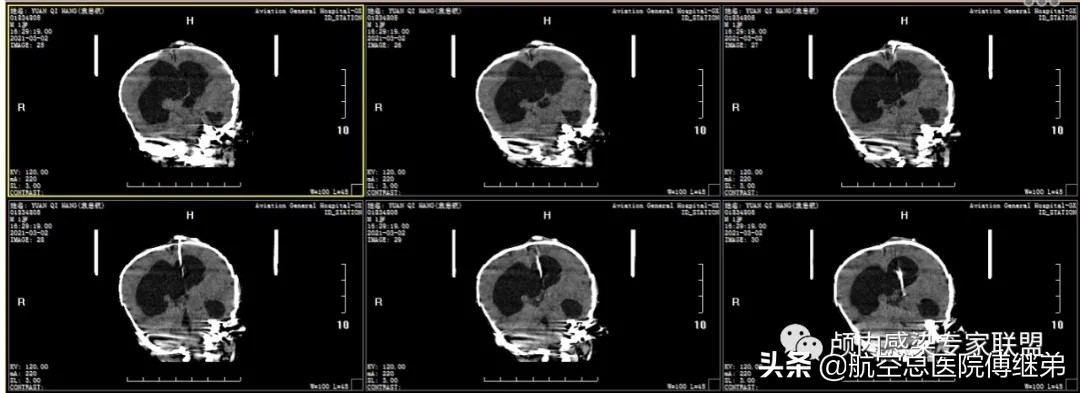

入院后完善相关检查,于2021-03-04在全麻下行脑室腹腔外引流术+原储液囊取出术。术后复查颅脑CT脑室引流管位置可(图六),术后早期引*脑流**脊液为淡黄色,患儿状态逐渐改善(图七)。

图六 术后复查颅脑CT脑室引流管位置可